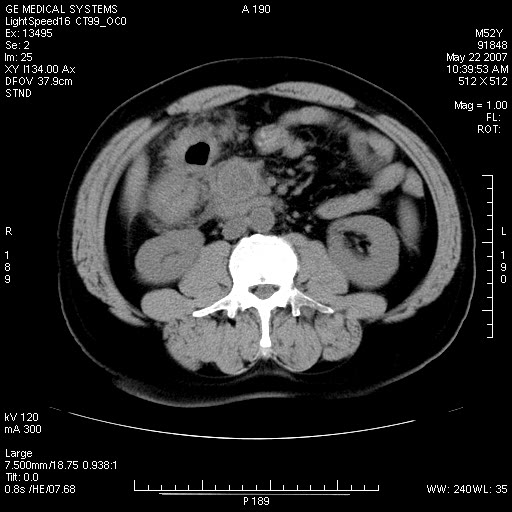

以下是引用余辉在2007-5-22 20:12:00的发言:[br]升结肠管壁明显增厚,增强有静脉期持续增强,结合患者病史,考虑结肠癌可能性大,临近脂肪影密度增高,混浊,恐有肠系膜浸润转移,建议镜检

以下是引用dyqct在2007-5-22 20:43:00的发言:[br]支持结肠肝曲占位性病变(浸润型结肠癌可能性大)。胆总管下端扩张,原因待查。

以下是引用gaoxiao在2007-5-22 20:49:00的发言:[br]考虑升结肠癌向周围侵犯,胰头钩突受侵。